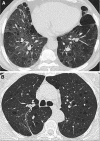

The diffuse cystic lung diseases (DCLDs) are a group of pathophysiologically heterogenous processes that are characterized by the presence of multiple spherical or irregularly shaped, thin-walled, air-filled spaces within the pulmonary parenchyma. Although the mechanisms of cyst formation remain incompletely defined for all DCLDs, in most cases lung remodeling associated with inflammatory or infiltrative processes results in displacement, destruction, or replacement of alveolar septa, distal airways, and small vessels within the secondary lobules of the lung. The DCLDs can be broadly classified according to underlying etiology as those caused by low-grade or high-grade metastasizing neoplasms, polyclonal or monoclonal lymphoproliferative disorders, infections, interstitial lung diseases, smoking, and congenital or developmental defects. In the first of a two-part series, we present an overview of the cystic lung diseases caused by neoplasms, infections, smoking-related diseases, and interstitial lung diseases, with a focus on lymphangioleiomyomatosis and pulmonary Langerhans cell histiocytosis.